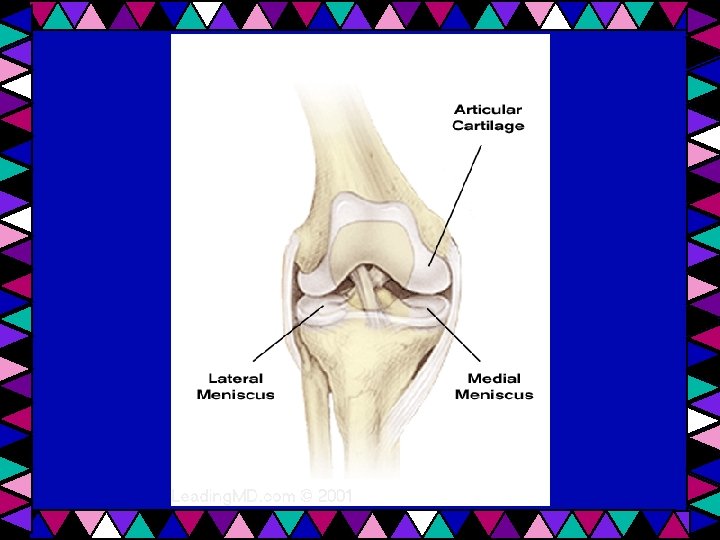

Cartilage • Hyaline • Elastic • Fibrocartilage

Fibrocartilage Withstands heavy pressure & tensile forces - Intervertebral disks - Knees and elbows

Fibrocartilage